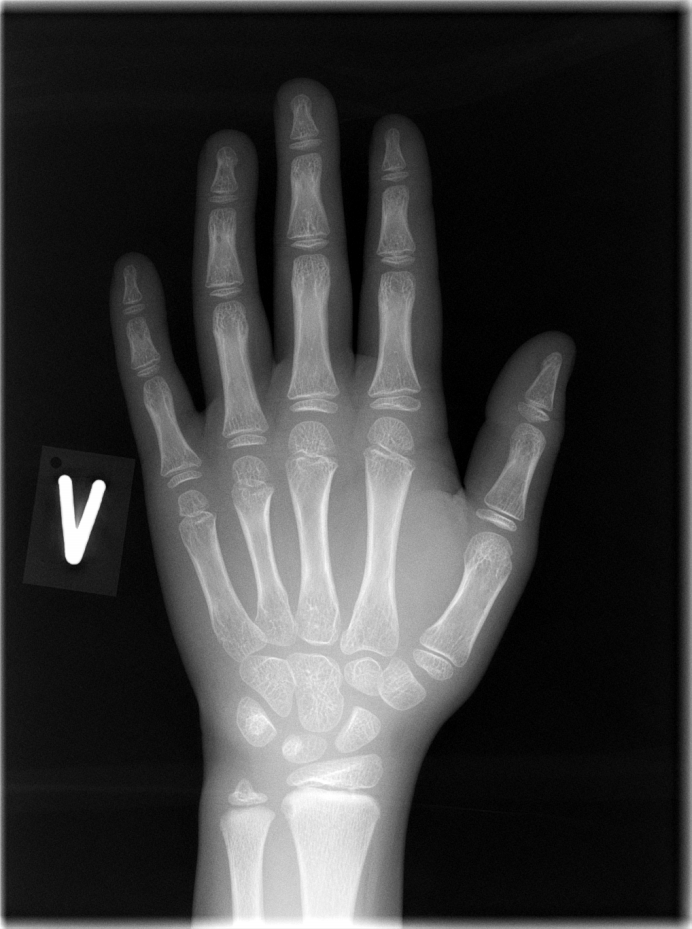

BoneXpert is a software for automated measurement of bone age from a child's hand X-ray image. 200 hospitals have already integrated this tool seamlessly into their workflow for more consistent readings when dealing with growth disorders, optimisation of treatments and state-of-the-art adult height prediction.

The workflow with BoneXpert Server is illustrated above: After an X-ray is recorded, it is stored in the local PACS. A PACS user (a radiographer or radiologist) can then send the image to BoneXpert for analysis. After 10-30 seconds, BoneXpert returns an annotated X-ray, which is stored in PACS as a new image under the same Study. The PACS user does not directly operate a BoneXpert user interface, what is seen is simply the result: an additional image with the results of the analysis as an overlay; an example is shown here:

The software is set up via the configuration user interface shown below. Once it has been configured and started, it requires no active operation. The service receives DICOM hand X-rays, locates the bones in the image, computes the bone age and bone health index, and returns the result to the PACS as an additional image (or data set) in the same study.